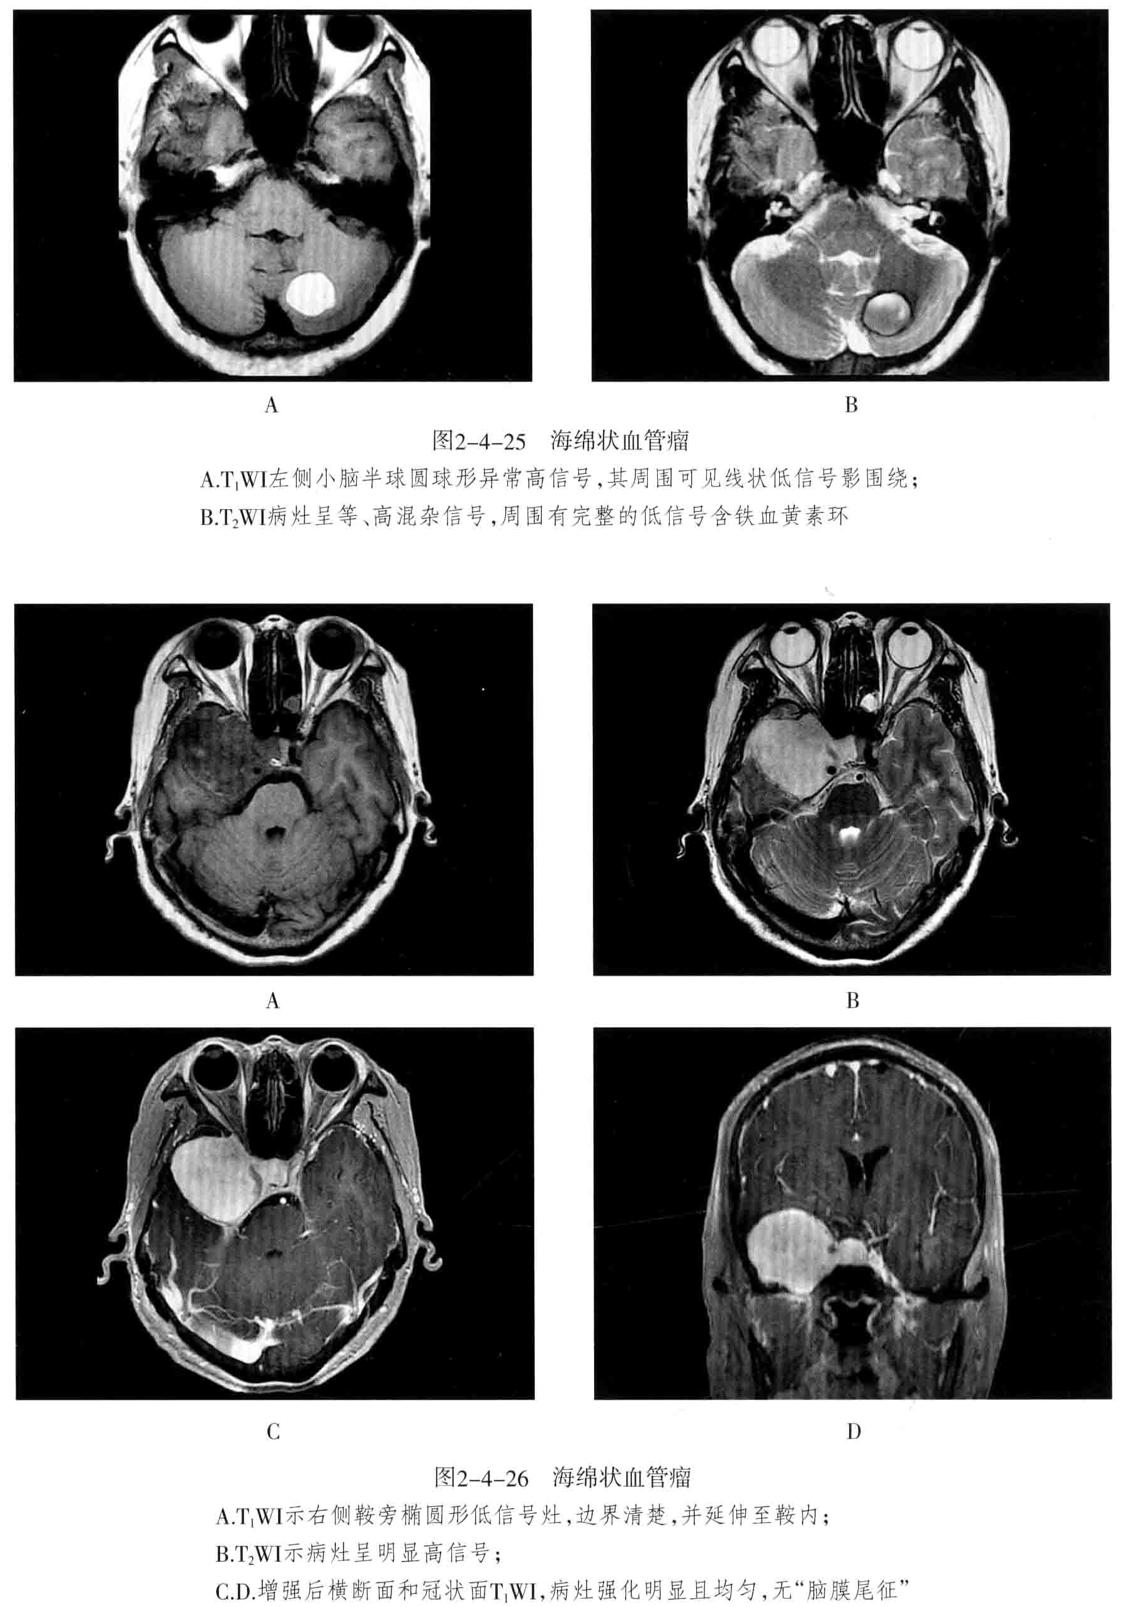

• 海绵状血管瘤 病变主要由不规则、大小不等的薄壁海绵状血窦组成,其间有增生的胶质组织,没有正常的神经组织,可反复少量出血,常有不同程度的钙化和含铁血黄素沉着。可发生于脑内(常见于大脑半球各叶)、脑外(常见于颅底)。常无任何症状,或表现为癫痫等。

2. CT检查:类圆形高密度或稍高密度病灶,边界清楚,病灶内密度多数不均匀,常伴有明显钙化,呈斑点状或斑块状。病灶周围一般无水肿。增强扫描出现不同程度强化。

3. MRI检查:T1WI多呈高信号、稍高信号或混杂信号,T2WI上呈高、低混杂信号,典型者呈“爆米花”状,境界清楚,病灶周围有含铁血黄素沉积,T2WI是表现为低信号环。病灶内及周边无流空血管影。病灶无占位效应,周围脑组织无水肿。大量出血时,表现为病灶短期明显增大,可有占位效应。增强后脑内者病灶可轻度强化,亦可无强化。脑外者多于颅底鞍旁,T1WI低信号,T2WI明显高信号,边界清楚,增强后明显强化且强化均匀。